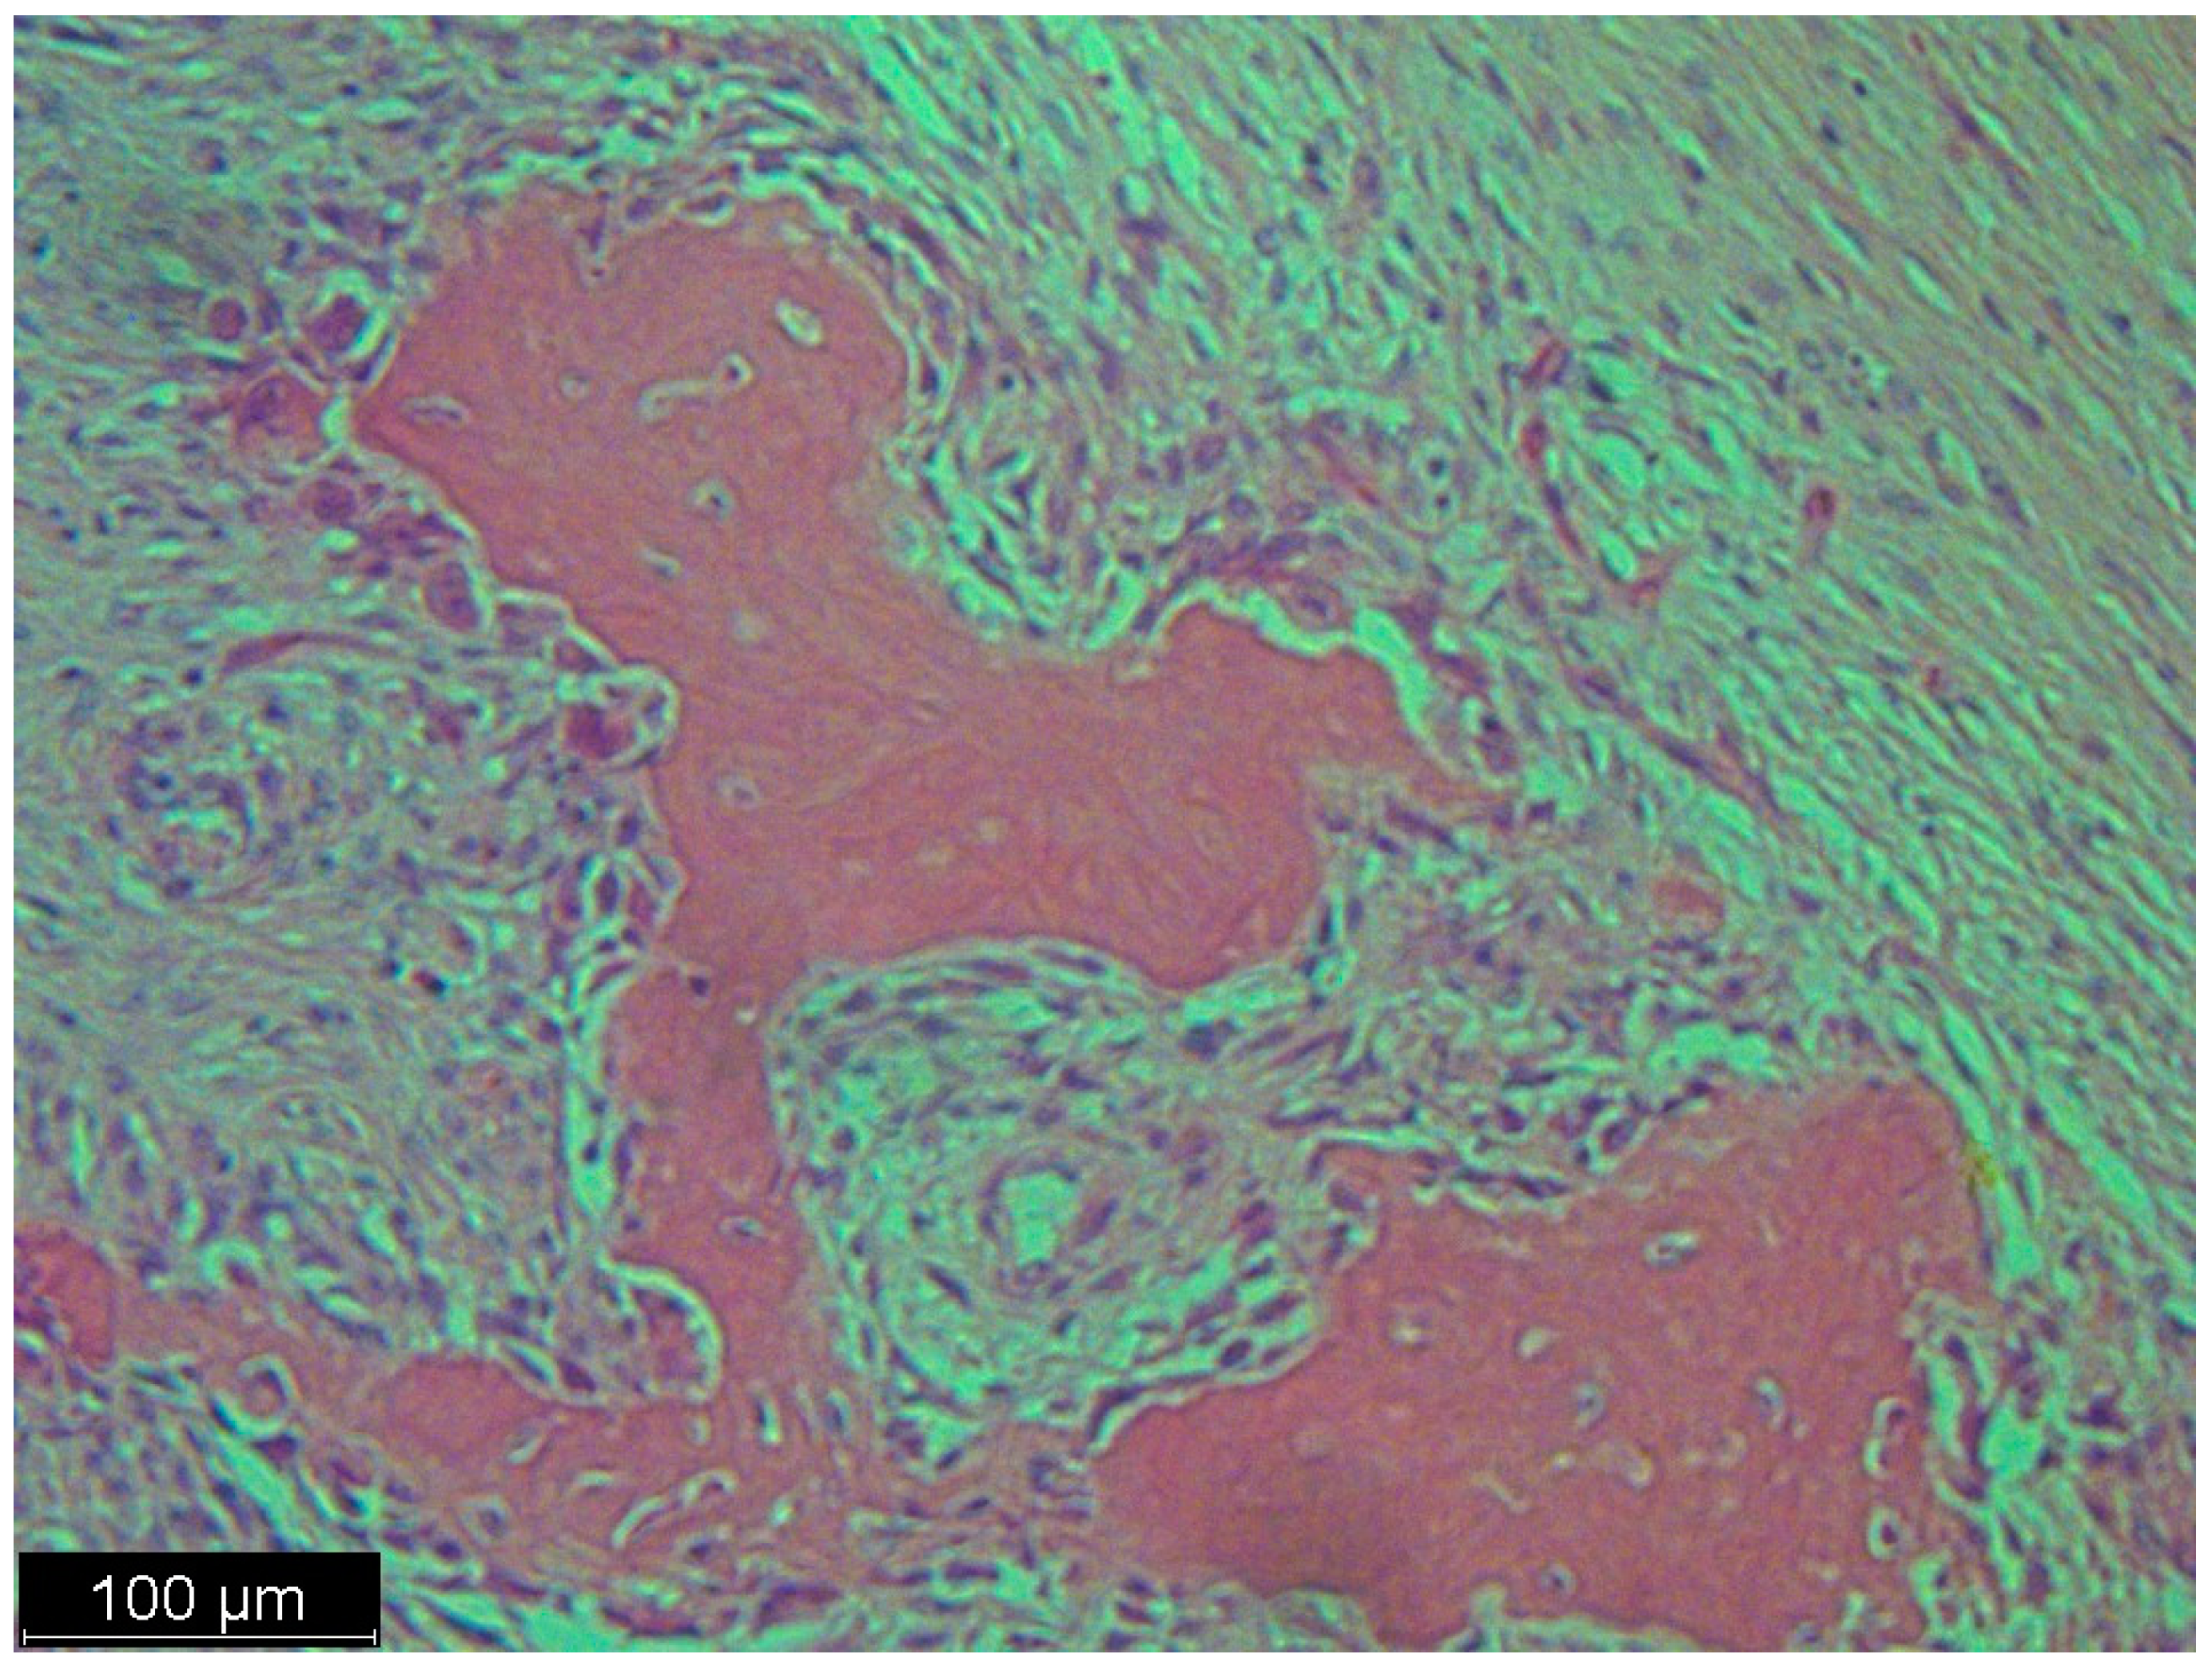

Figure 4.

A low magnification of the tumor showed a nodular mass. The nodules were formed from multinucleated giant cells and mononuclear cells. Interspersed among these structures were spindle cells, some of which were pleomorphic and some of which were simply dark and hyperchromatic. This was not a typical case, because in the textbook definition of dedifferentiated liposarcoma, there are parts of well-differentiated liposarcoma and atypical squamous cells which we did not see in this case; there were just scattered spindle cells and a heterologous component.